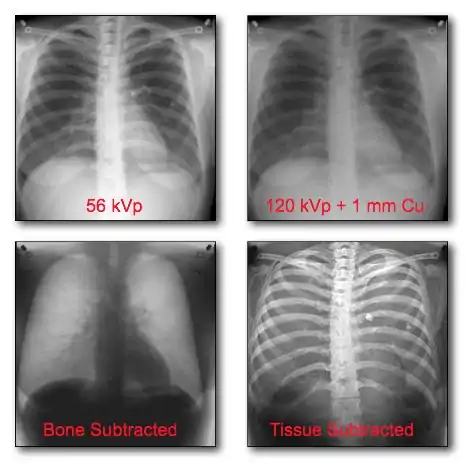

Dual-Energy Imaging

- CR and DR image receptors can generally be used for dual-energy radiography in either of two configurations:

- Dual exposures: where two separate exposures are used in applications where patient movement isn't an issue; and

- Single exposure: where two imaging plates separated by a filter are mounted in a dual-energy cassette to record the low energy image on the anterior plate and the high energy image on the other.

- The form of image data processing is illustrated in Figure 7.17.

- A chest radiograph acquired at 56 kV is shown in the top left panel of the figure. This is referred to as a low energy image. In the top right panel is a radiograph of the same patient's chest acquired at a high energy - 120 kV, with 1 mm copper filtration. Results of the dual-energy processing are shown on the bottom row. The bone-subtracted image is shown in the bottom left panel and the tissue-subtracted image in the bottom right panel. Notice that the tissue-subtracted image demonstrates that the lesion in the patient's left lung is a calcified nodule, since it doesn't appear in the bone-subtracted image. Simulated X-ray spectra for the two different kilovoltages are shown in Figure 7.17a to illustrate the energy separation that can be achieved using these exposure factors.